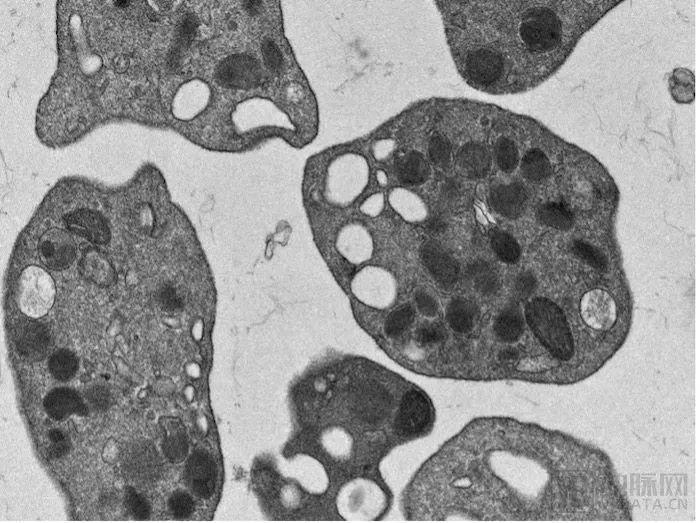

血小板电镜图,血霁生物提供

血小板是身体中唯一负责凝血的细胞,它的缺乏会带来全身性的出血,脏器与颅脑出血常伴随不可逆的损伤,乃至危及生命。临床上对它的诉求几乎覆盖医院各科室,也是供应最为紧张、最需要反复输注的成分血。然而全球血小板的供应都靠献血来源,这不仅受到献血率的影响,而且会成为传染疾病的传播媒介。在出现公共卫生事件时,比如新冠疫情期间,血小板的供应更加停摆,造成了很多伤害。朱博士对本媒体表示,她收到了好多问询,表示他们正在寻找血小板,他们真心期待血霁能带来新的曙光。这也让朱博士及团队更加砥砺前行、不懈奋斗。

除了临床输注止血的刚需,血小板参与了血栓形成、癌症监控、损伤修复等过程,为血栓类疾病、癌症、运动医学、衰老治疗、医美等各领域都提供了独特的解决方案。血霁生物将会紧扣血小板的核心,以干细胞体外再生的技术获得原料,推动其向相关领域的辐射,并且积极完成技术原研和专利布局,并开始向生产转换。